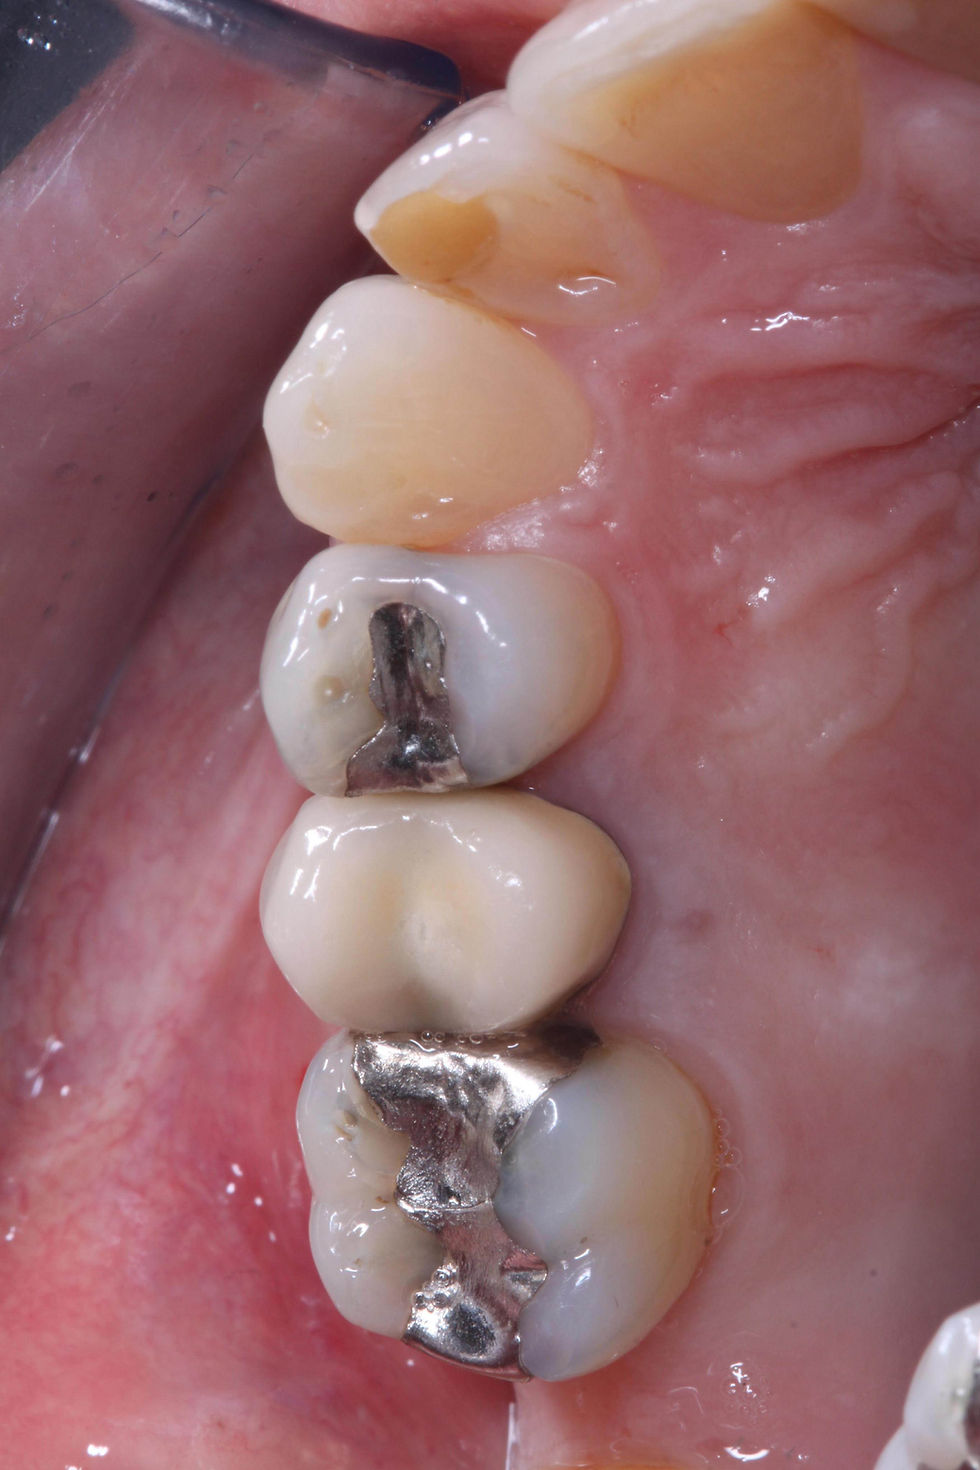

Initial clinical images of the crown on the 1.5.